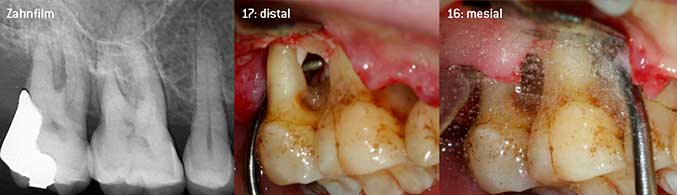

Als Initiatoren zur Entwicklung der neuen diamantierten Luftscaler-Spitze 3AP sahen es beide Zahnärzte als notwendig an, die Einschränkung in der Handhabung bisher kommerziell vermarkteter diamantierter Spitzen insbesondere während der Furkationstherapie oder in engen Knochentaschen zu verbessern. Dies sollte unabhängig von nicht-chirurgischem (Abbildung 2) oder chirurgischem Vorgehen sein (Abbildung 3).

(Fotos Abb 2 -4: © Dr. Chr. Graetz)

Das Ziel bestand darin, eine universell einsetzbare Spitze zu entwickeln, um zeitraubende Spitzenwechsel zu vermeiden. Daneben sollte aber die Anwendung der neuen Arbeitsspitzen sowohl in engen Knochentaschen von distal als auch am distalen Furkationseingang von Oberkiefermolaren einfacher sein und infolgedessen eine effektivere Instrumentierung ermöglichen. Dies wurde durch einen größeren Durchmesser des Instrumentenbogens (Abbildung 1) erreicht, was gerade bei Zähnen mit fortgeschrittenem Attachmentverlust und Furkationsbeteiligung von großem Vorteil während des geschlossenen Debridements ist (Abbildung 4).